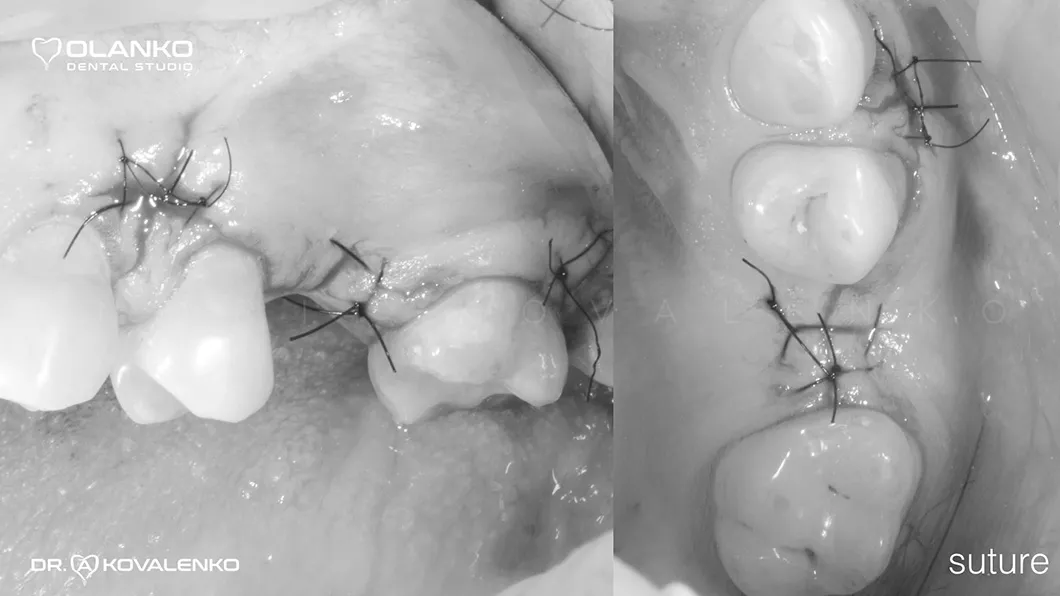

*Фотографии с наличием крови были переведены в черно-белый формат

Ситуация после установки коронки ДО/ПОСЛЕ

Ситуация после установки коронки до и после Оланко Бровары Киев